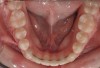

Figure 3 “Before” photograph of an adult patient with significant periodontal disease and recession with some teeth that historically might have been considered “hopeless.”

Figure 3

Figure 4 “After” photograph of the same patient in Fig 3 showing the significant benefit of orthodontic treatment on the health of the teeth and gums.

Figure 4